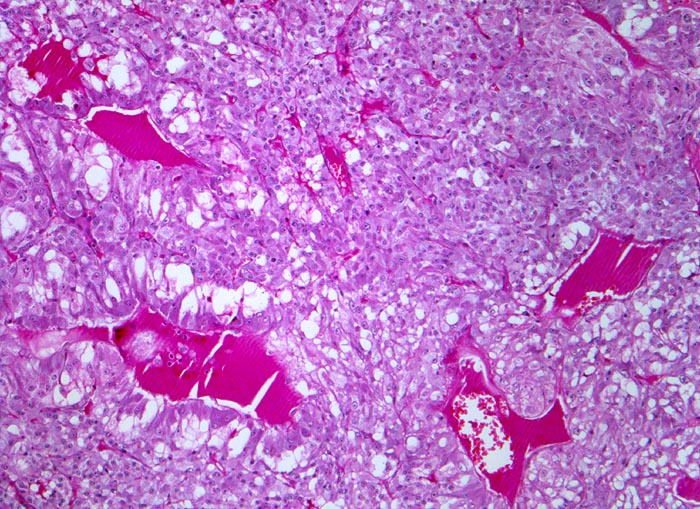

Phaeochromozytom

Nebenniere

«Zellballen» aus teils spindelig konfigurierten, grossen Tumorzellen. In den Bindegewebssepten um die Zellballen lassen sich zahlreiche dilatierte Blutgefässe nachweisen.

Der Patient klagt über rezidivierende Kopfschmerzen seit zirka zwei Monaten. In letzter Zeit hat er Alcacyl genommen, jedoch ohne Erfolg. Die Computertomographie des Abdomens zeigt einen 5cm grossen Tumor im Bereich der rechten Nebenniere. Die Familienanamnese für multiple endokrine Neoplasien (MEN) ist bland.